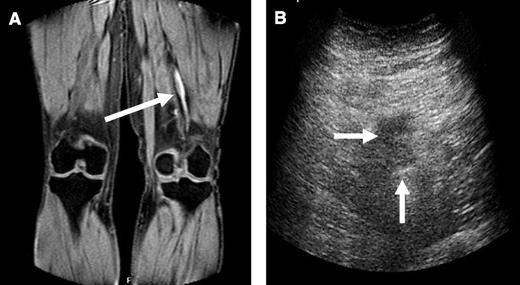

MRDTI was abnormal in 37 of 39 patients of group 1 with symptomatic recurrent ipsilateral DVT. For two patients in this group, the MRDTI images were judged as normal. In the first 57-year-old male patient, recurrent DVT was demonstrated by CUS in a new proximal segment (popliteal vein) when compared with the original ultrasonography of his first DVT in the femoral vein only 10 months earlier (Table 1). The D-dimer level at the moment of suspected recurrence was 1195 ng/mL. The ultrasonography result of the second 18-year-old male patient was judged to be a more propagated thrombotic obstruction of the popliteal vein with new extension into the popliteal segment below the knee when compared with the ultrasonography of the first DVT diagnosed 17 months earlier. His D-dimer level at the most recent presentation of suspected recurrent DVT was 584 ng/mL (Table 1). The onset of symptoms of DVT was less than 48 hours in both patients, and neither reported respiratory or chest symptoms indicative of the presence of acute PE. MRDTI images and corresponding ultrasonography images are displayed in Figure 1 for a patient from study group 1 with acute recurrent ipsilateral DVT.

Abnormal signal on MRDTI in the popliteal vein of the left leg. (A) Arrow indicates positive MRDTI signal in a patient with symptomatic and CUS-proven ipsilateral recurrent DVT in the popliteal vein; (B) arrows indicate incompressibility of corresponding vein on ultrasonography.

MRDTI was normal in all 42 patients of group 2, who had chronic thrombosis on CUS and no symptoms of acute recurrent DVT. Figure 2 depicts the normal MRDTI signal in a patient from study group 2 with asymptomatic residual thrombosis.

The sensitivity of MRDTI was 95% (95% CI, 83% to 99%), and specificity was 100% (95% CI, 92% to 100%; Table 2). By using a selected group of study participants with an overall 48% frequency of acute recurrent DVT, the negative predictive value of MRDTI was 95% (95% CI, 83% to 98%), and the positive predictive value was 100% (95% CI, 88% to 100%).